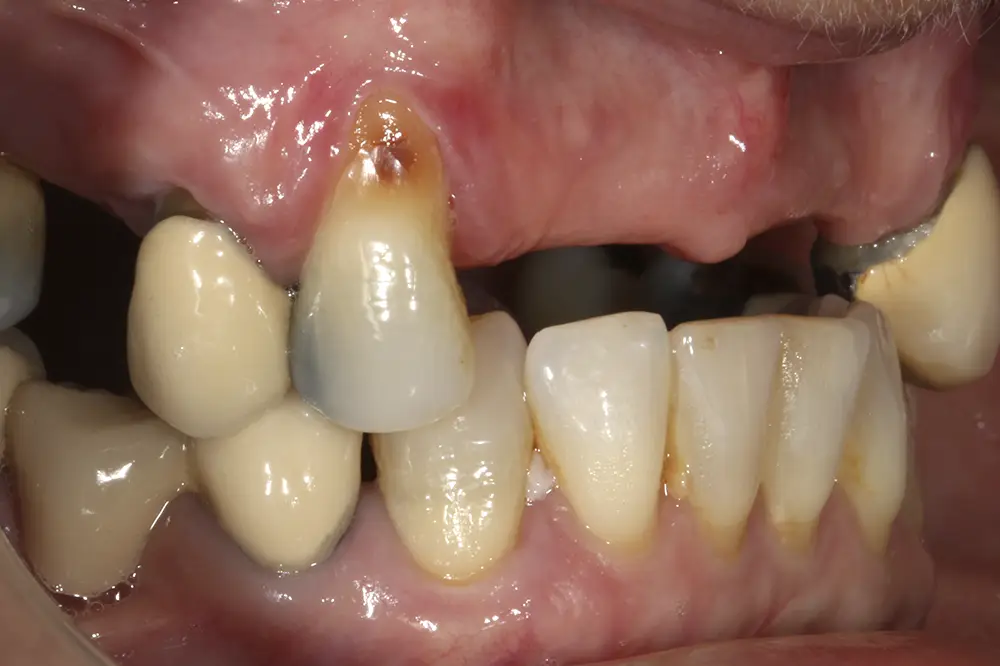

Al retirar las prótesis en las imágenes laterales, observamos además un colapso de la zona anterior y recesiones en todas las piezas que aún conserva la paciente (figs. 5 y 6). En la radiografía inicial observamos pérdidas óseas elevadas en el molar del primer cuadrante y el premolar de este mismo sector, por lo que se decide su exodoncia y regeneración con PRGF, que se realizará el mismo día de la primera fase de inserción de los implantes. En el arco inferior hay también problemas con los sectores posteriores, con pérdidas óseas en el cuarto cuadrante y signos de fractura vertical en el puente 44-46 y caries radicular en las piezas 35 y 36 (fig. 7). Por ello, estas piezas inferiores son también candidatas a la exodoncia, regeneración y reposición con implantes dentales, para lograr una posterior rehabilitación funcional.

Figs. 5 y 6. Imágenes laterales de la paciente sin su prótesis. Al retirarla, se hace evidente el colapso de la dimensión vertical y la pérdida ósea y recesión de los dientes pilares que sostienen la prótesis removible.